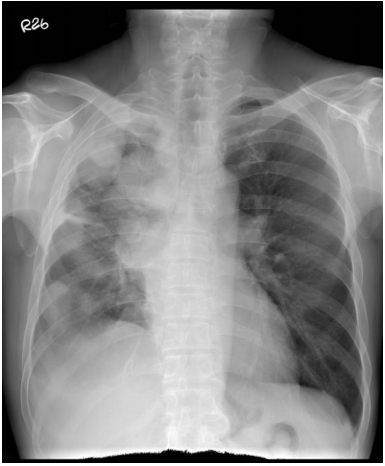

12. 71歲男性病人因為咳嗽三周,胸部X光意外發現左肺有陰影。電腦斷層檢查顯示(如圖示)左下葉有一顆腫瘤及右氣管前有一顆1公分淋巴結,頭部電腦斷層及骨骼掃描皆無異常。請問接下來的檢查何者最有效率,可以在最短的時間得到治療所需要的資訊? (A) 先做電腦斷層接片檢查確認為惡性後,再做正子斷層造影,淋巴結有異常再做縱膈腔鏡淋巴取樣。 (B) 先做電腦斷層接片檢查確認為惡性後,再做正子斷層造影,淋巴結有異常再做支氣管超音波經氣管淋巴結抽吸。 (C) 先做支氣管超音波周邊腫瘤切片,再做正子斷層造影。淋巴結有異常再做支氣管超音波經氣管淋巴結抽吸。 (D) 先做支氣管超音波經氣管淋巴結抽吸,確認為惡性腫瘤,如果為良性同時做支氣管超音波周邊腫瘤切片後,再考慮正子斷層造影。 (E) 先做正子斷層造影,確認無其他轉移再做電腦斷層切片檢查。